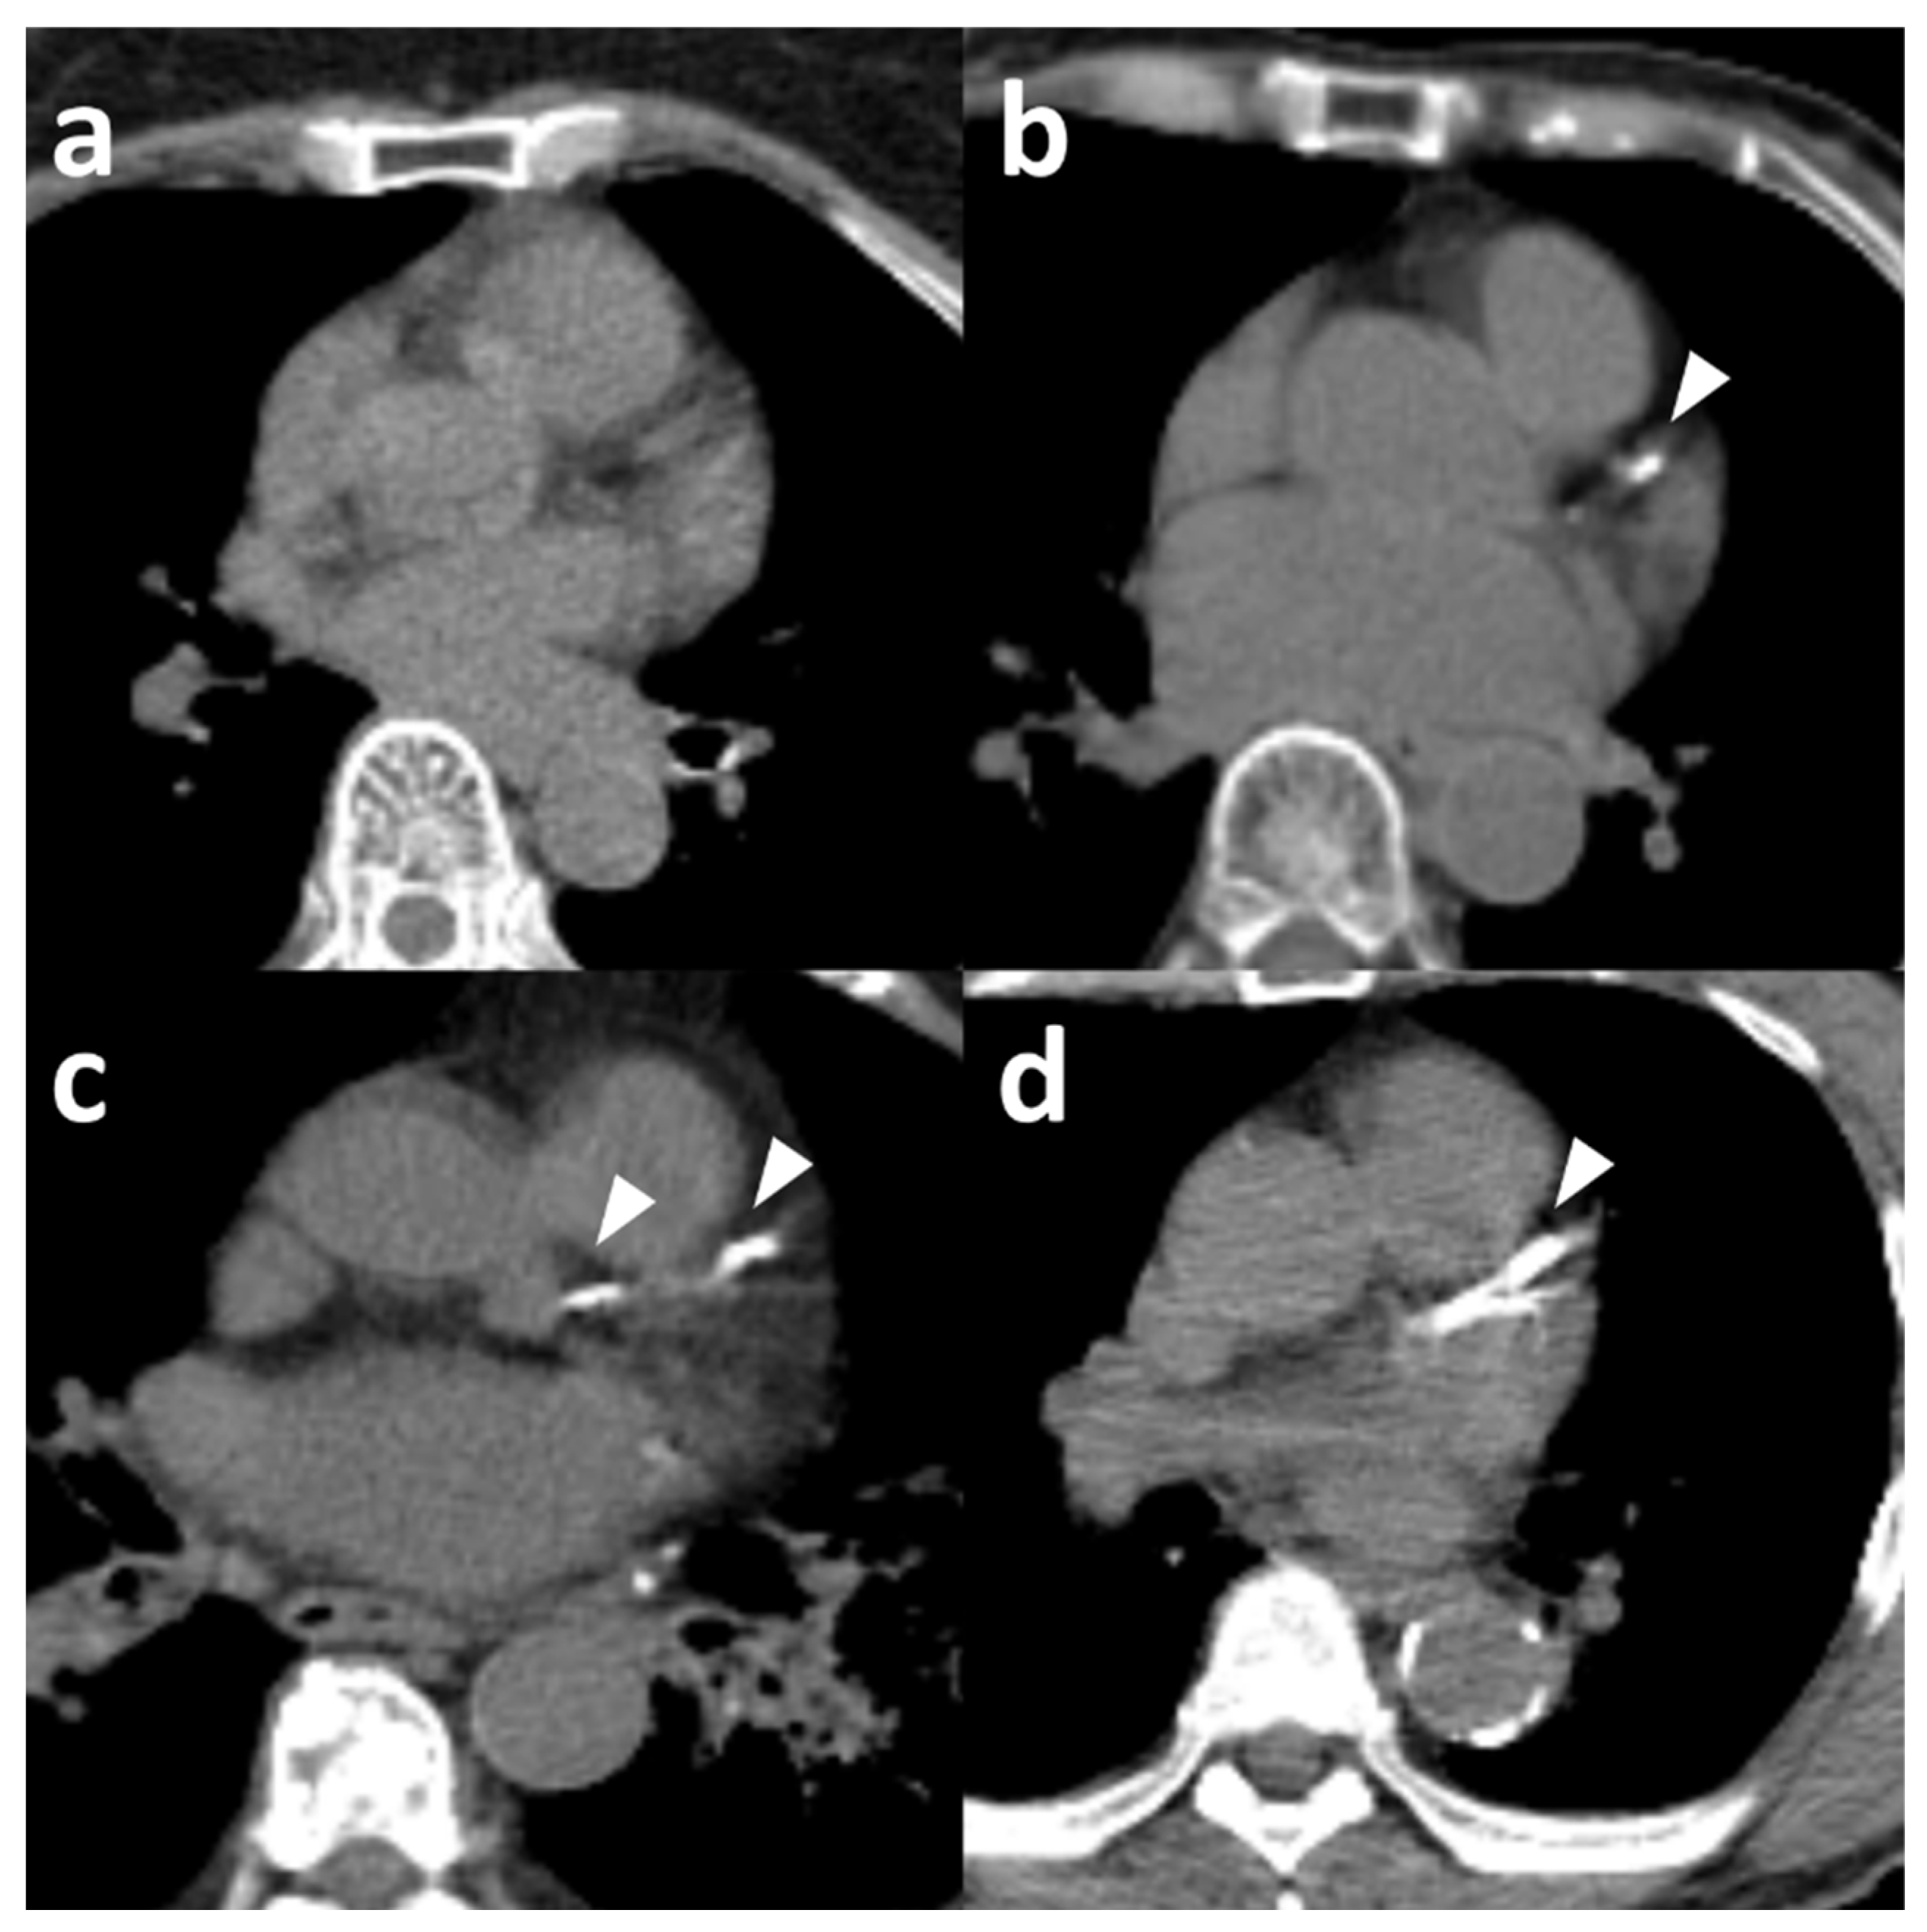

3.2. Interobserver Agreement of Standard Visual and Ordinal Scales on PET/CT

3.3. Concordance with Agatston Score Categories from ECG-Gated Chest CT